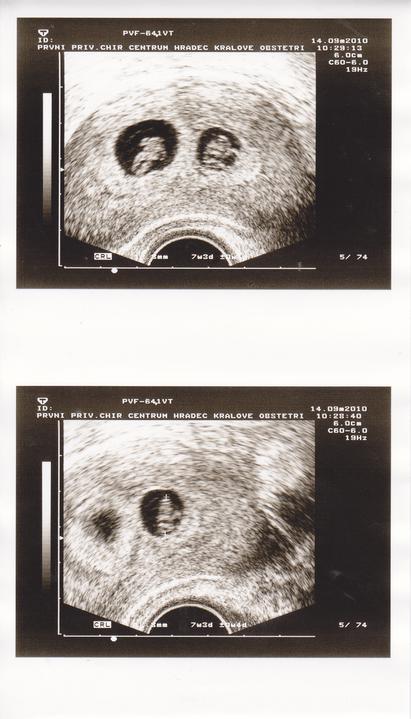

31 srpna-ultrazvuk-Pan doktor našel 2 oplodněná vajíčka,jedno menší,druhé větší.